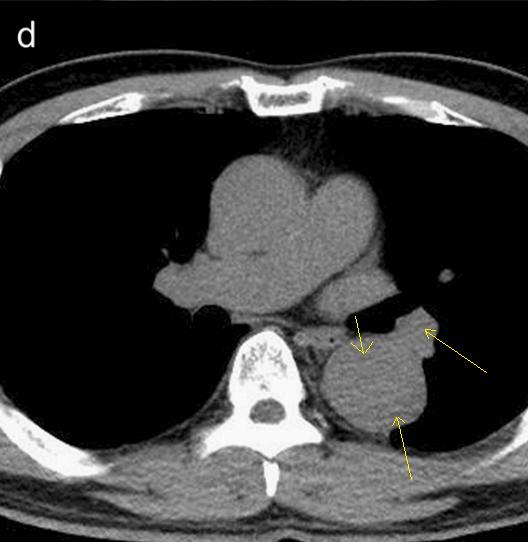

病例9

下面这个CT平扫,似乎有大问题!

图22

什么问题?似乎这里有大问题!

图23

同学,你眼神太好使了!

很可惜,这个不是问题,很多CT平扫都有这种线样阴影!

做个增强CT一看,哇,同学,你不光眼神好,运气也不是一般的好!

图24